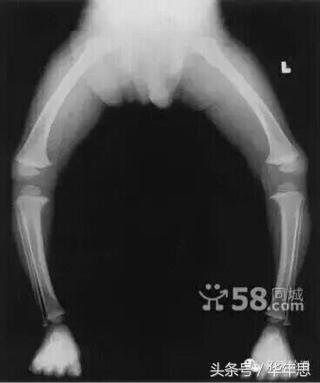

穿上这些不合格的轮滑鞋,您的孩子会有多少伤害?